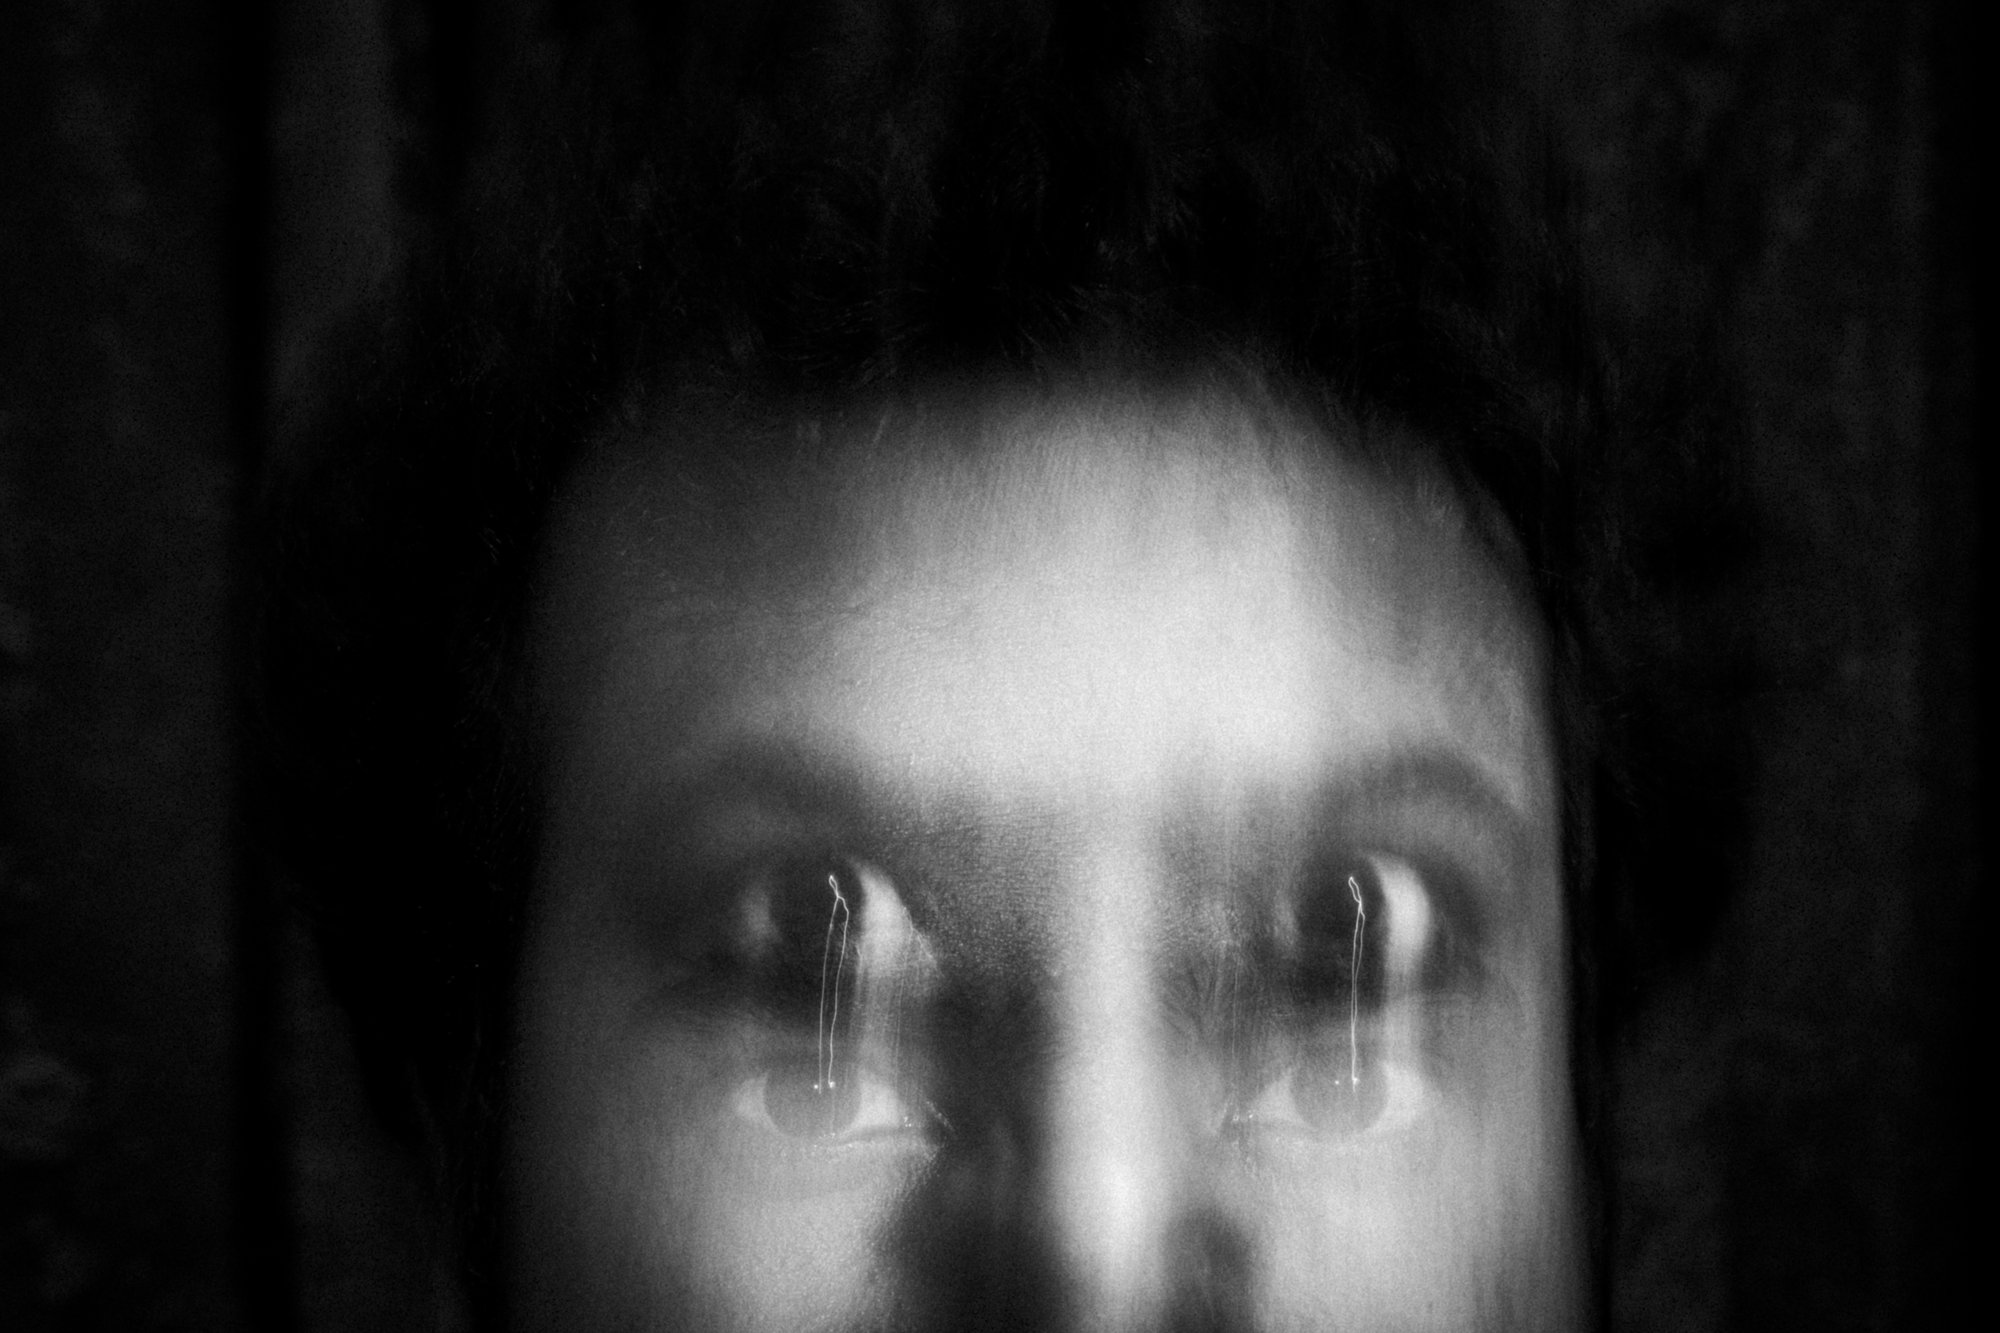

This is an ongoing personal documentation of my chronic pain – migraine. Migraine is considered a regular headache yet the sufferer had to endure 4-5 helpless hours of pain and I have been experiencing this pain for last 20 years. This project is a continuous portray of every attack I endured over the last few years. I'm currently photographing these moments with my camera and my mobile device. The purpose of this essay is to depict the underlying cause of migraine including bright light, loud sound, strong smell and its treatments such as discipline life, intake of water, brain mapping, etc. Currently, I have been healed around 80-90% thereby incorporating minor lifestyle changes and some basic medications. "Parallel Life - Migraine Chronicles" is my artistic endeavour, born from empathy and a desire to shed light on the oft-hidden agony of migraines. Through the lens of my camera, I have embarked on a visual odyssey to unveil the visceral, emotional, and deeply human journey of those grappling with this debilitating condition.